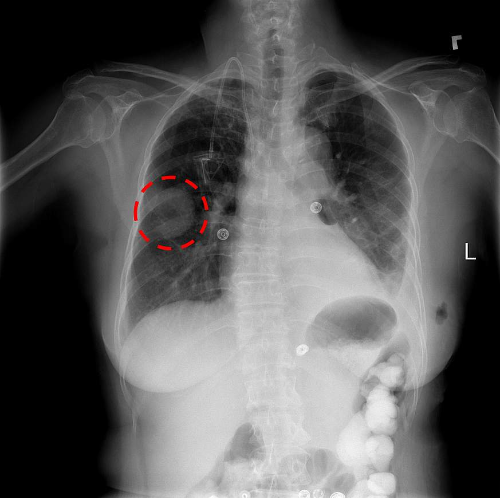

1. 흉부 X-ray 촬영

폐암 검사방법 중 가장 일반적인 검사의 하나로 엑스레이 촬영이 있습니다. 가장 기초적인 검사이고 가장 빠르기도 합니다. 하지만 이 방법은 폐암 세포가 5mm 이상 자란 상태에서 발견할 수 있습니다. 때문에 극 초기의 경우에는 발견하기가 어렵다고 합니다. 또한 흉부 X-ray 촬영은 심장 주변부나 뼈와 겹치는 부분은 확인이 어려울 수 있습니다.